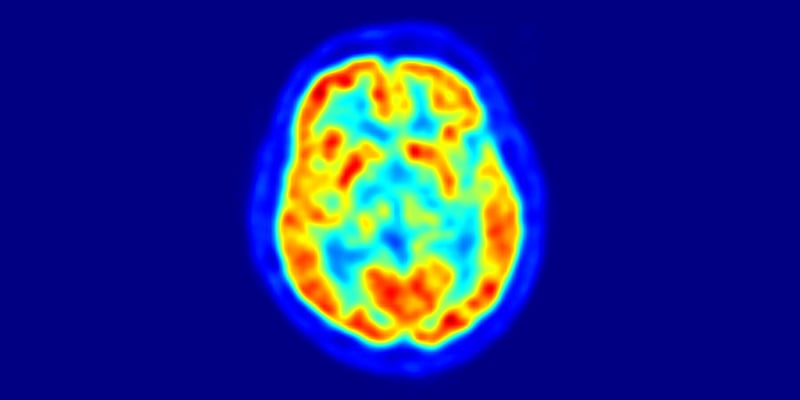

Nuclear medicine procedures administer tiny amounts of radiopharmaceuticals to a patient to obtain functional information about organs, tissues and bone. A special camera is used to detect gamma rays emitted by the radiopharmaceuticals and create an image of the body part under study. The information is recorded on a computer screen or on film.

This is a transaxial slice of the brain of a 56 year old patient (male) taken with positron emission tomography (PET) / Image © Jens Maus, Public Domain

Nuclear medicine imaging